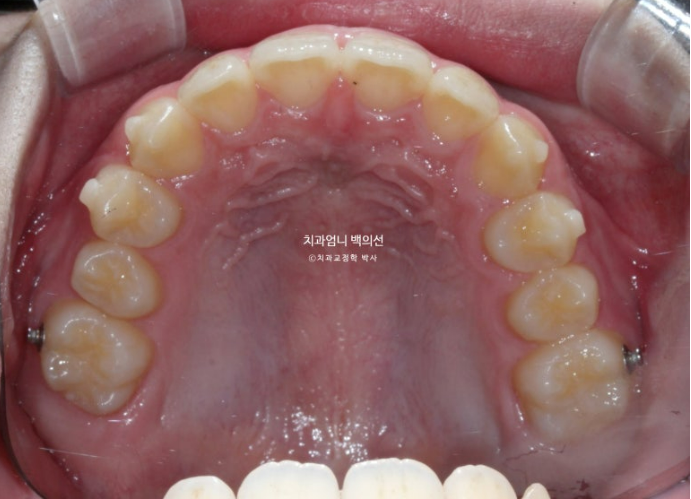

25년 5월 두번째 세트 21개 장치를 모두 낀 후 드디어 치료를 마무리 했습니다.

25.05

앞니 깊게 물리는 과개교합은 해결이 되었고 중심선은 잘 맞습니다.

어금니 교합은 1급 교합관계입니다.